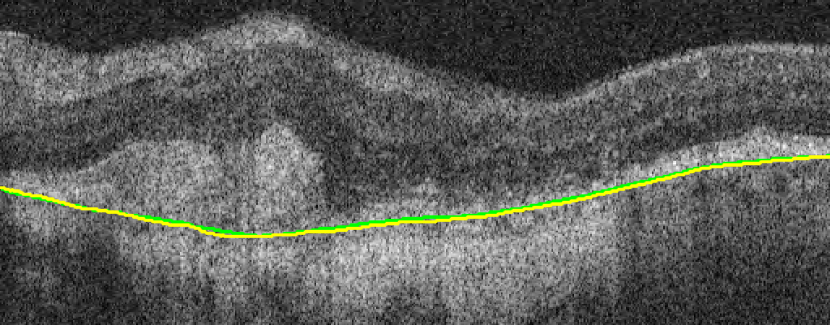

Bruch’s Membrane is an elastic smooth and thin structure, strategically located between the retina and the general circulation, having a crucial role in retinal function, aging and disease [14]. Automated segmentation of the BM is particularly important in the context of AMD as, unlike other common retinal diseases such as DR, RVO, or glaucoma, the BM is distinguishable from the outer RPE boundary. In specific, drusen in iAMD and PEDs in nAMD separate the RPE from BM, requiring the segmentation of the region in-between them. In addition, in case of GA, the RPE is completely lost in some locations, exposing only the BM, thus imposing additional difficulties for algorithms and calculations that depend on the RPE position. Achieving correct automated identification of the BM is challenging in many cases, mainly due to the small thickness of this layer, the high reflectivity of the RPE that shadows parts of the BM, and the noise being present in the scans, which is often indistinguishable from the content of drusen and PEDs (Fig. 4). Due to these difficulties, currently many automated solutions either do not provide a segmentation of the BM or its segmentation is often inaccurate in retinal OCT with AMD, leaving this clinically relevant segmentation task unaddressed or under-explored.

(a) iAMD